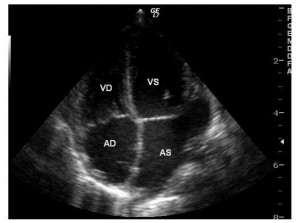

Ecocardiografia a depistat o malformaţie cardiacă congenitală simplă: defect septal interatrial (DSA) larg, tip ostium secundum, cavităţi drepte mult dilatate (atriu drept, ventricul drept, artera pulmonară), hipertensiune pulmonară (presiune pulmonară medie: 40 mmHg), defect septal interventricular muscular apical mic, insuficienţă mitrală uşoară (Figura 1, 2).

Figura 1. Ecocardiografie transtoracică incidenţă apical 4 camere: dilataţie de cavităţi drepte, defect septal interatrial tip ostium secundum. AD: atriu drept, VD: ventricul drept, AS: atriu stâng, VS: ventricul stâng.

În aceste condiţii sugarul a fost din nou transferat în serviciul de chirurgie cardiacă. S-a realizat cateterismul cardiac care a confirmat suspiciunea ecocardiografică de origine anormală a arterei coronare stângi din artera pulmonară (Figura 5). S-a reintervenit chirurgical. Intraoperator s-a observat originea arterei coronare stângi la nivelul bifurcaţiei arterei pulmonare, posterior, având un trunchi comun destul de lung. S-a realizat implantarea arterei coronare stângi în aortă. Evoluţia post-reintervenţie a fost bună, cu instalarea unei bune creşteri ponderale ulterior. Ecocardiografia a ilustrat noua origine a arterei coronare stângi din aortă (Figura 6), absenţa şuntului la nivelul septului interatrial şi ventriculul stâng revenit la o contractilitate bună (Figura 7); insuficienţa mitrală era uşoara şi persista defectul septal interventricular muscular apical mic. Electrocardiograma s-a normalizat (Figura 8). La 3 ani de la intervenţie copilul este asimptomatic şi are o dezvoltare psihosomatică corespunzătoare vârstei.

Figura 7. Ecocardiografie transtoracică incidenţă parasternal ax scurt: vizualizarea originii corecte a arterei coronare stângi din aortă.

Figura 8. Ecocardiografie transtoracică incidenţă apical 4 camere: dimensiuni normale ale ventriculului stâng, absenţa defectului septal interatrial. AD: atriu drept, VD: ventricul drept, AS: atriu stâng, VS: ventricul stâng.